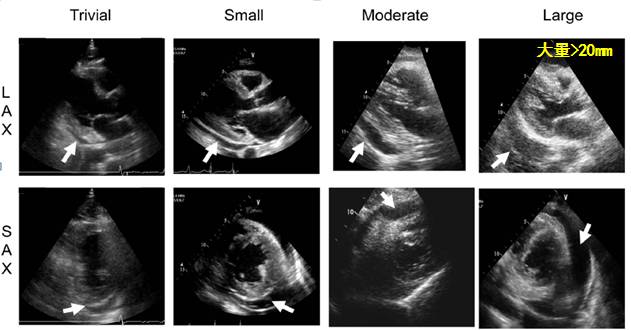

心包积液分类和处理的简单流程

l超声心动图是一线检查